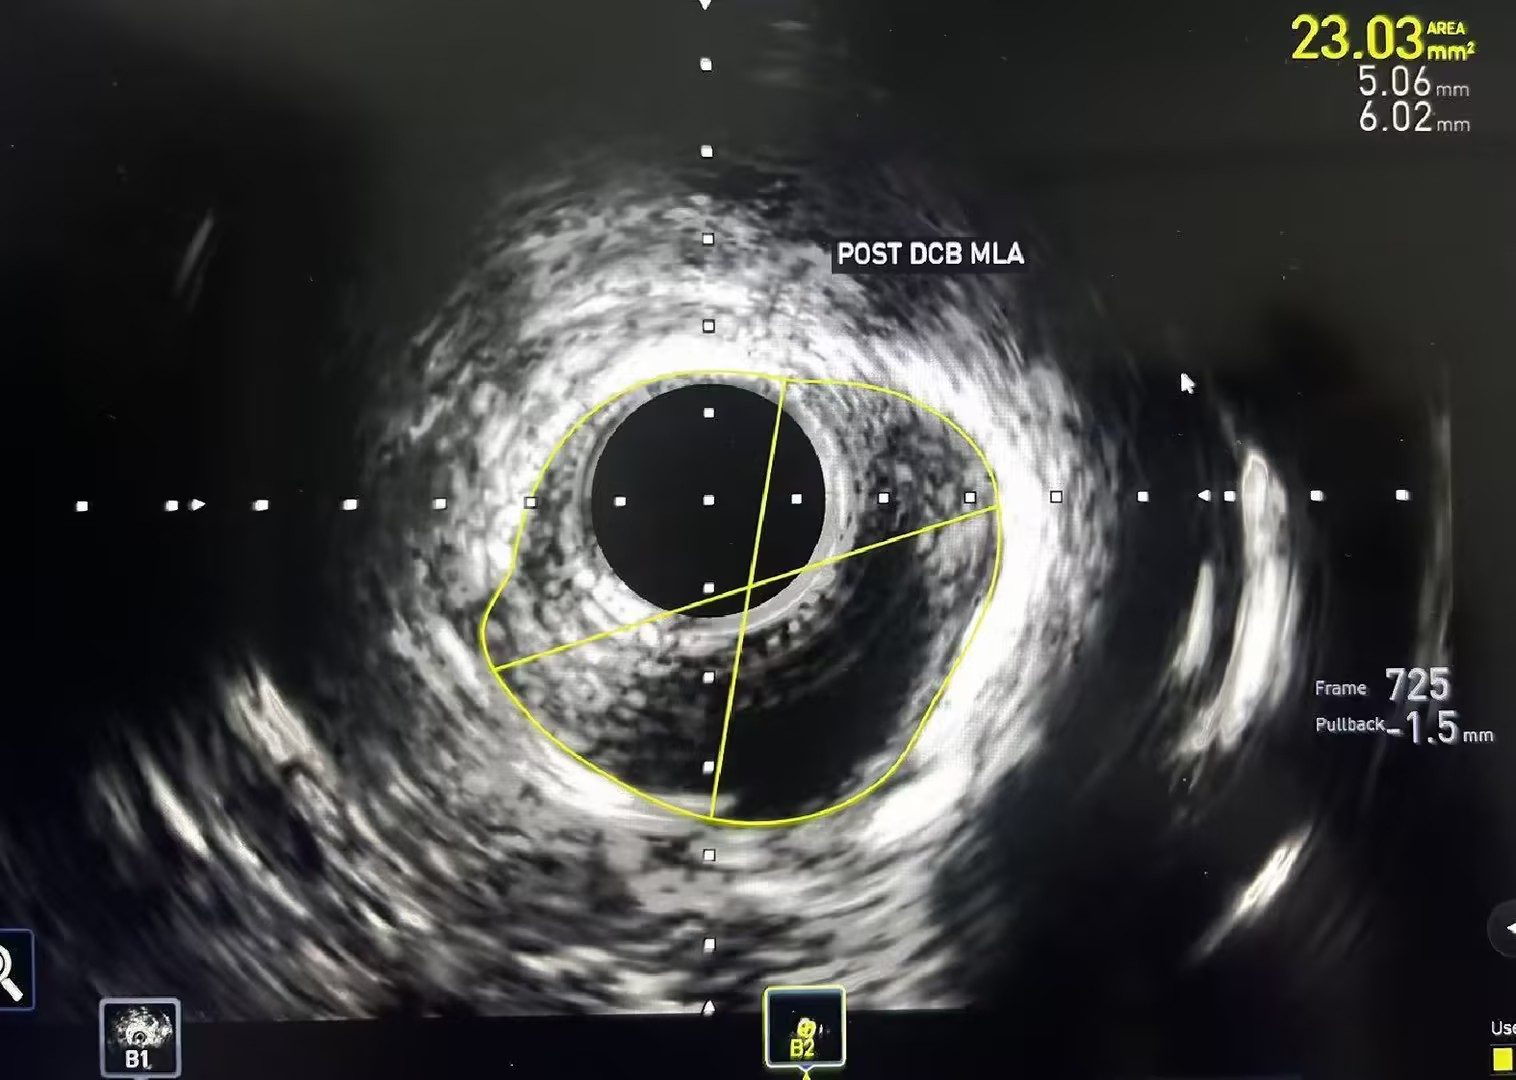

图4 术后IVUS:官腔面积约23m㎡ 官腔内血流通畅,钙化斑块断裂

手术中,血管外科副主任赵俊来团队经穿刺将一根纤细的超声导管送入目标血管。这根导管能360度旋转,实时生成血管横截面的高清图像,把血管内部的情况“一览无余”。通过IVUS,首先看清钙化的“真面目”,精准定位钙化斑块的分布、厚度和范围,确认了其呈环周型分布;其次,测量出了管腔的“精确尺寸”,IVUS不受钙化影干扰,能精准测量血管的真实直径,为选择球囊和支架提供了“毫米级”的数据支持,避免了“小鞋大脚”或“大鞋小脚”的尴尬;最后,它还完成了斑块的“质地评估”,帮助判断是软斑块、纤维斑块还是混合斑块,这对制定后续手术策略至关重要。

在IVUS的精准导航下,赵俊来团队为患者制定了“震波球囊+药物涂层球囊”的黄金组合方案。第一步,使用震波球囊。在IVUS指引下,球囊精准定位至钙化最严重处,发出声压力波,安全地“敲松”了坚硬的内膜下钙化环。这一步如同在坚硬的冻土上松土,IVUS实时验证了钙化环已被打开,血管弹性恢复,为后续扩开血管打好了基础。第二步,使用药物涂层球囊进行充分扩张,并将抑制内膜增生的药物精准涂抹于病变处,防止血管再次狭窄。IVUS再次确认了管腔获得充分、均匀的扩张,血流通道被成功重建。